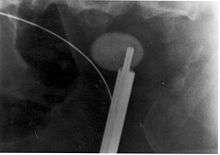

Ureteroscopy has become increasingly popular as flexible and rigid fiberoptic ureteroscopes have become smaller. One ureteroscopic technique involves the placement of a ureteral stent (a small tube extending from the bladder, up the ureter and into the kidney) to provide immediate relief of an obstructed kidney. Stent placement can be useful for saving a kidney at risk for postrenal acute renal failure due to the increased hydrostatic pressure, swelling and infection (pyelonephritis and pyonephrosis) caused by an obstructing stone. Ureteral stents vary in length from 24 to 30 cm (9.4 to 11.8 in) and most have a shape commonly referred to as a "double-J" or "double pigtail", because of the curl at both ends. They are designed to allow urine to flow past an obstruction in the ureter. They may be retained in the ureter for days to weeks as infections resolve and as stones are dissolved or fragmented by ESWL or by some other treatment. The stents dilate the ureters, which can facilitate instrumentation, and they also provide a clear landmark to aid in the visualization of the ureters and any associated stones on radiographic examinations. The presence of indwelling ureteral stents may cause minimal to moderate discomfort, frequency or urgency incontinence, and infection, which in general resolves on removal. Most ureteral stents can be removed cystoscopically during an office visit under topical anesthesia after resolution of the urolithiasis.[93]

More definitive ureteroscopic techniques for stone extraction (rather than simply bypassing the obstruction) include basket extraction and ultrasound ureterolithotripsy. Laser lithotripsy is another technique, which involves the use of a holmium:yttrium aluminium garnet (Ho:YAG) laser to fragment stones in the bladder, ureters, and kidneys.[94]